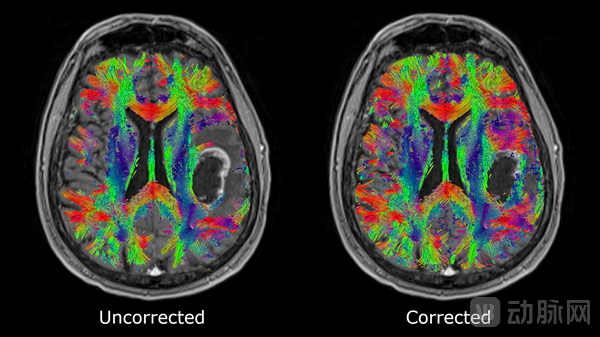

2022年年底,Synaptive推出了Modus Plan的新功能“Reveal”。这项新专利能对全脑纤维束图进行动态的自由水平校正,恢复显示脑损伤周围通常会被扩散信号遮挡的区域图像(如水肿区域)。搭载AI技术的Modus Plan可以在几秒内自动定位到患者的特定纤维束。

自由水平校正软件:Reveal

图源:Synaptive Medical官网